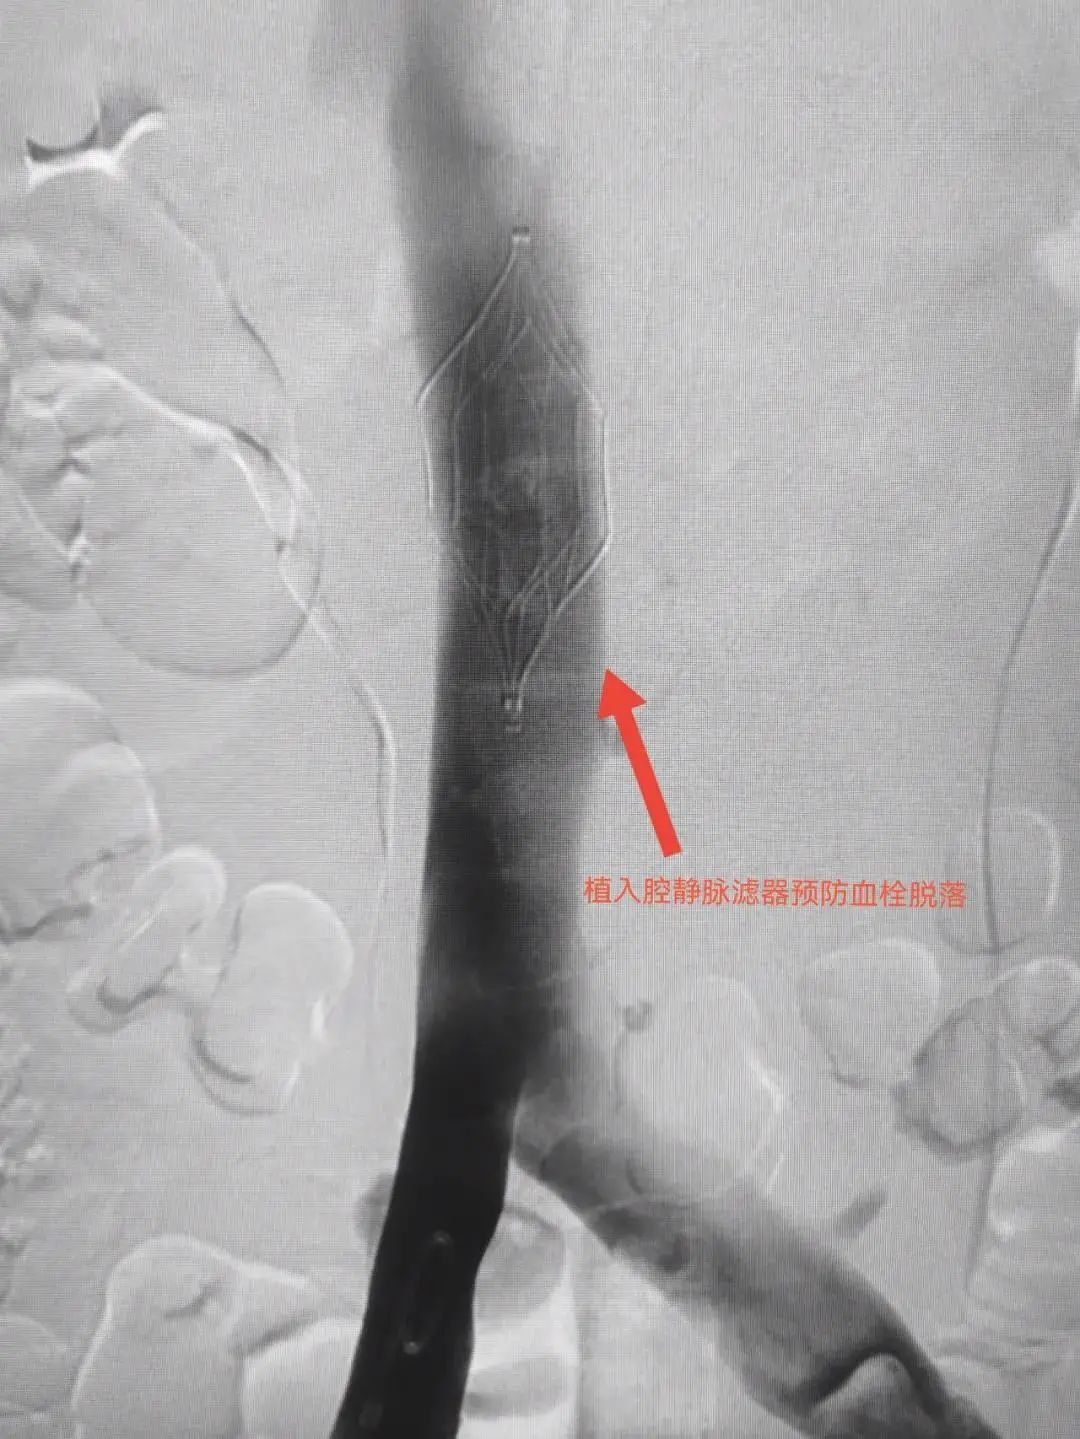

在邓节喜主任的指导下,介入科石荣跃副主任与何秋瑞主治医师配合默契,在患者下腔静脉植入静脉滤器(预防下肢静脉血栓继续脱落至肺动脉),并留置溶栓导管进行肺动脉溶栓,才把患者从死亡线上拉回来,手术圆满完成。